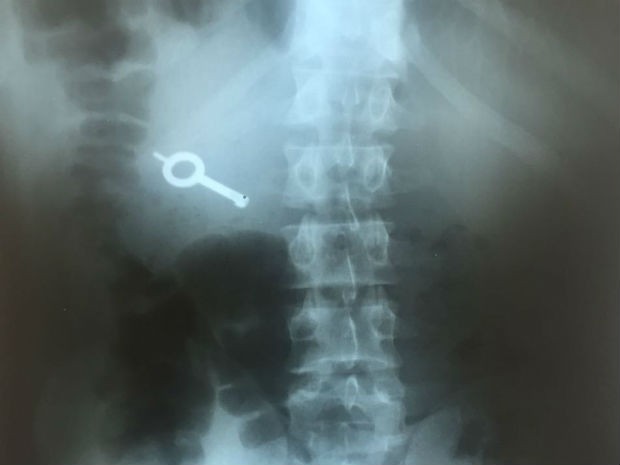

Raio-X mostra chave engolida por preso durante rebelião no Paraná

13/12/2016 às 04h16